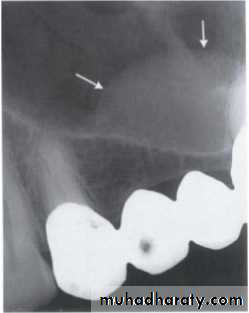

Blending border into adjacent area –gradual transition-normalappearing bone & abnormal appearing trabeculae -sclerosing osteitis• Invasive irregular border-bone destruction-malignancy.

Blending border. A gradual transition from the dense trabecular of sclerosing osteitis (short arrow) to the normal trabecular pattern (long arrow).• C:Shape